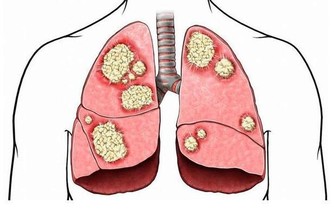

發燒是人體對發炎造成的反應,也是身體發出的一種警訊,

也因此大部分的爸爸媽媽都覺得發燒是件相當危險的事情,

只要孩子一發燒,就急著給他們吃退燒藥,怕連續高燒下孩子的腦袋瓜會燒壞了。

但適度的發燒對身體來說反而是件好事,

因為發燒等於身體的免疫系統正在與細菌、病毒對抗,很多研究發現,

人類生病時發燒,算是一種保護性的本能反應,目的在加強我們對於疾病的抵抗力。